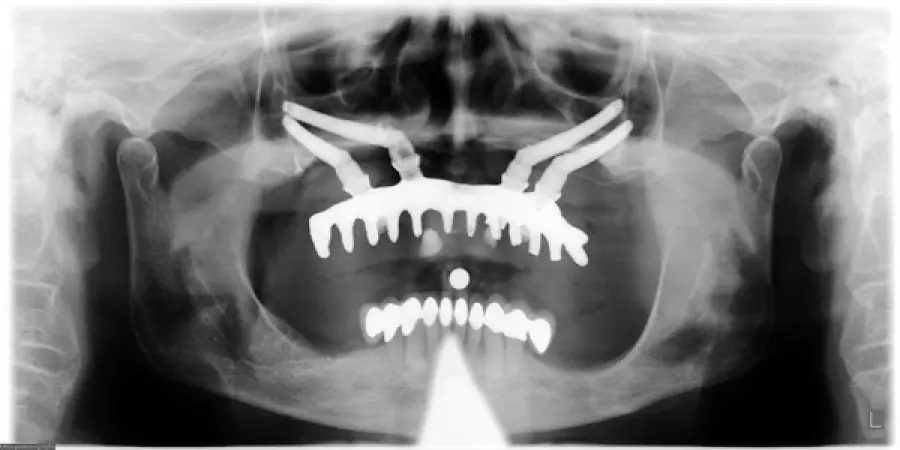

Quando si tratta di ‘posizionamento nel mascellare superiore’ l’impianto viene messo in modo da evitare il ‘recesso mesiale del seno mascellare’ stesso.

Se invece si tratta del ‘posizionamento nel mascellare inferiore’ l’impianto viene ubicato in maniera tale che si evita ‘l’emergenza del nervo alveolare inferiore’.

Gli impianti inclinati offrono una grande attendibilità ed efficienza poiché sono ancorati in modo così ottimale in quel che rimane dell’osso mascellare, che una volta posizionate le protesi, il carico immediato avviene simultaneamente.

Questa tecnica sta riscuotendo notevole successo poiché mette in evidenza prerogative abbastanza interessanti su quella che è la ‘riabilitazione immediata di edentulie complete sia in mascella che in mandibola’